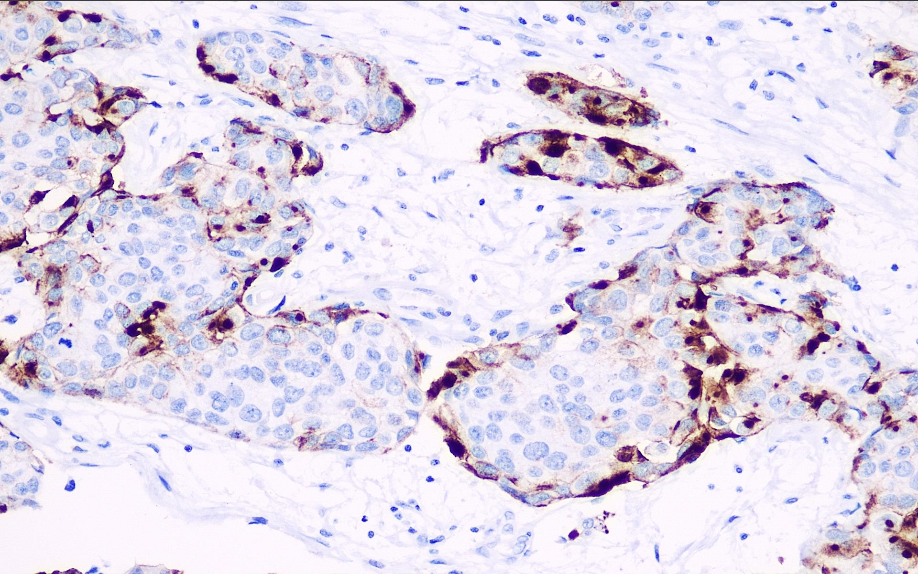

Cellular localization: cytoplasm/membrane

Positive control: bladder/translocated cell carcinoma

Uroplakins (UPs) are members of a family of transmembrane proteins involved in the differentiation of bladder epithelial cells. Uroplakin III is expressed in both primary and invasive bladder epithelial carcinomas but is not expressed in many non-urinary tract epithelial tumors, thereby aiding in the study of bladder epithelial carcinomas. The Uroplakin III gene is lost in normal urinary tract epithelium and after malignant metastasis in bladder cancer, and may manifest as urinary tract epithelial tumors with malignant potential, serving as a reference for cellular differentiation in urinary tract epithelial cells. Patients with Uroplakin III-positive bladder epithelial carcinoma have a higher relative survival rate.

Uroplakin III antibody reagents can specifically bind to the Uroplakin III molecular antigen. Immunohistochemistry kits containing Uroplakin III antibody reagents are suitable for the auxiliary diagnosis of bladder epithelial carcinoma.